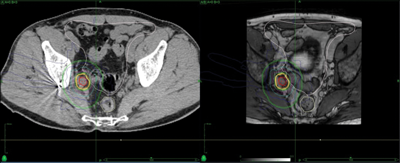

A 66-year-old man presented with a locally advanced T3b N1 prostate cancer in 2011, with an initial PSA of 33. He was treated with robotic prostatectomy and lymph node dissection followed by adjuvant prostate bed radiotherapy. Although immediate post treatment PSA levels were undetectable he had a PSA relapse in September 2012 to 2.1. Whole body MRI and Choline PET showed an apparent isolated left iliac lymph node recurrence (Figure 4). He went on to receive stereotactic radiotherapy (33Gy in 3 fractions to the lymph node - Figure 5). Follow-up imaging has shown a complete radiological response within the treated node. Eighteen months after treatment his PSA has started to rise again and most recent imaging has shown the development of a lymph node on the opposite side of the pelvis with no other sites of disease. He subsequently had further stereotactic radiotherapy to the right pelvic side wall nodes in July 2014. His PSA has dropped to 0.02 on his most recent check in January 2015.

Figure 5: Stereotactic radiotherapy plan to isolated pelvic lymph node showing marker in situ.